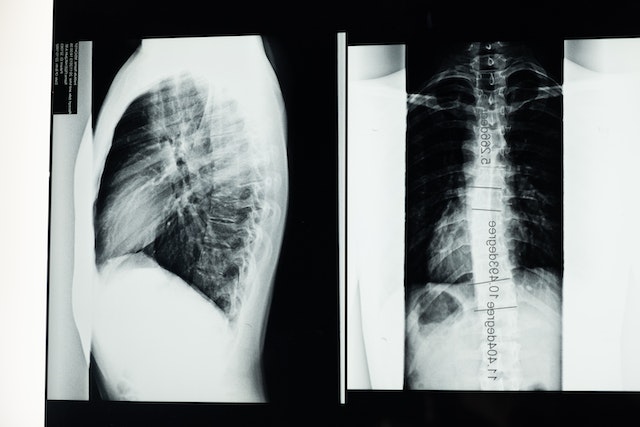

La escoliosis se entiende como una curvatura lateral anormal en la columna vertebral, es decir, la desviación hacia la izquierda o la derecha de la columna vertebral. Si se observa la columna vertebral desde delante o detrás, esta debe ser recta, mientras que vista de perfil tiene cuatro curvaturas (naturales).

La escoliosis es una desviación lateral de la columna.